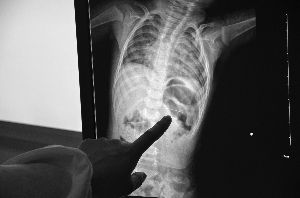

X光片里,绣花针完全扎进左肾,取出后已断成两截

1月11日上午,医生为小烁烁实施了手术,取出了一根长约3.5厘米的绣花针。

“绣花针能扎入这么深,确实少见,一般来说,即使不小心扎到孩子,也只会刺入皮下组织或者肌肉,但现在基本上整根针都插进了左肾。”小儿外科副主任医师黄岭竹说,从刺入的角度接近90度和深度来看,不排除人为刺入的可能,但这个需要警方调查。另外,医生发现从烁烁体内取出的绣花针针鼻子(针尾的小孔,用于穿线)已经断裂,断裂部分至今还没找到,CT检查也没有发现孩子体内留有金属物质。

王登峰小心翼翼地保存着从儿子体内取出的绣花针,昨天上午,这根用餐巾纸包好的针突然断成了两截,他估计针在孩子体内有一段时间了。他准备今天早上赶回丹阳后巷派出所报案。